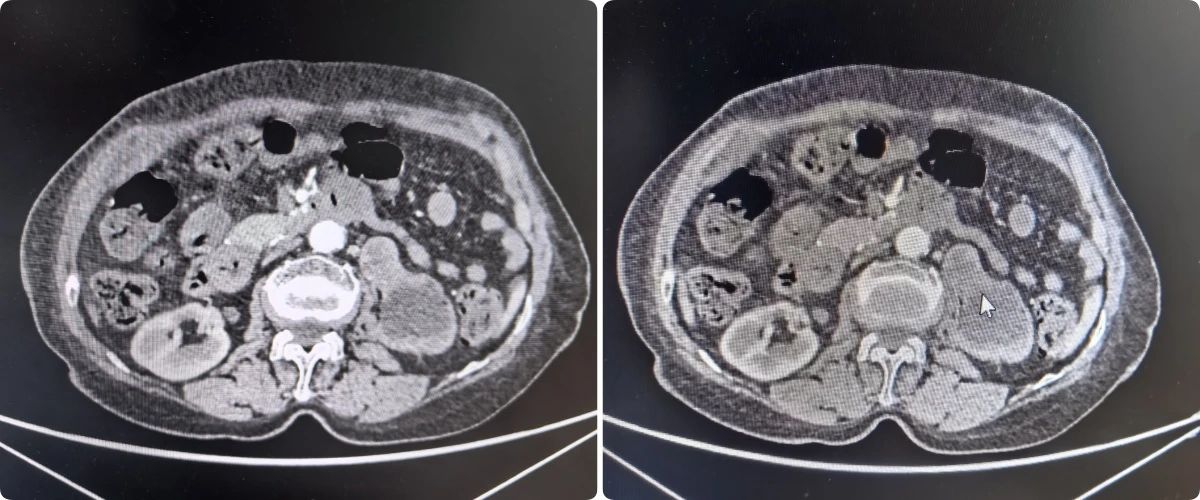

病例1:一位因排尿困难就诊的患者,在细致检查后被确诊为右肾占位性病变(倾向恶性),并伴有前列腺增生。面对复杂病情,我院泌尿外科团队在充分术前评估与多学科会诊的基础上,精心制定了分阶段治疗方案。首先解决患者排尿难题,随后择期实施了腹腔镜下肾根治性切除术,实现了对病灶的精准切除。患者术后恢复良好,生活质量得到提升。病例2:患者因右侧肾盂结石反复泌尿道感染,经抗炎治疗效果不佳。泌尿外科团队决定采用经尿道输尿管软镜肾盂激光碎石取石术,手术成功,感染得到控制。病例3:患者因“尿频、夜尿增多”来院拟行前列腺手术。入院进一步CT检查发现左肾肿瘤、考虑恶性。团队经充分评估,行腹腔镜下肾根治性切除术。病例4:一例无痛性肉眼血尿患者,经增强CT确诊输尿管占位性病变后,行腹腔镜下左侧肾输尿管全长及部分膀胱切除术。腹腔镜下肾切除术有什么优势呢?